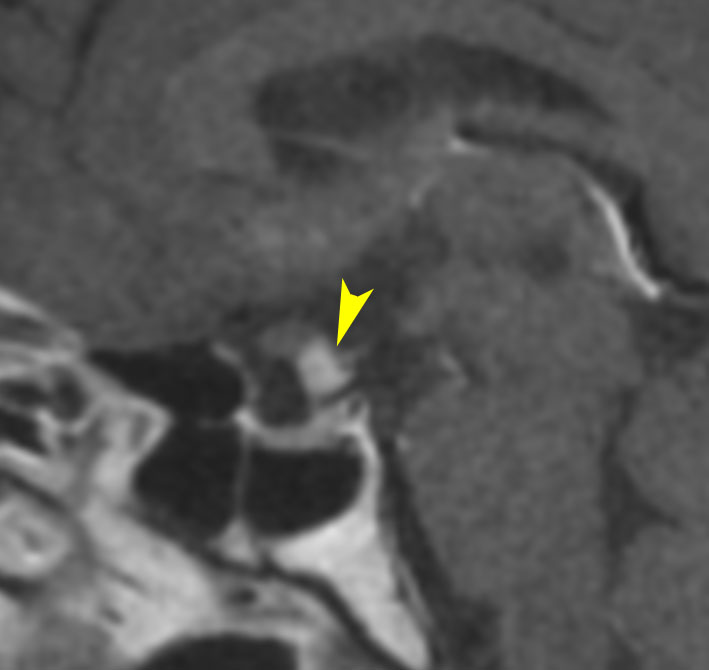

7歳の子が視力障害で発症しました。両耳側半盲という症状です。典型的な鞍隔膜下頭蓋咽頭腫です。ガドリニウム造影剤を入れないMRIでみえる,黄色い矢印の先の白い高信号は抗利尿ホルモンです。ですから下垂体機能もまだ残っていて,尿崩症はありません。視力障害が戻らないことがあるのでなるべく早く,経鼻的な手術で摘出した方がいいものです,簡単 o(^-^)o